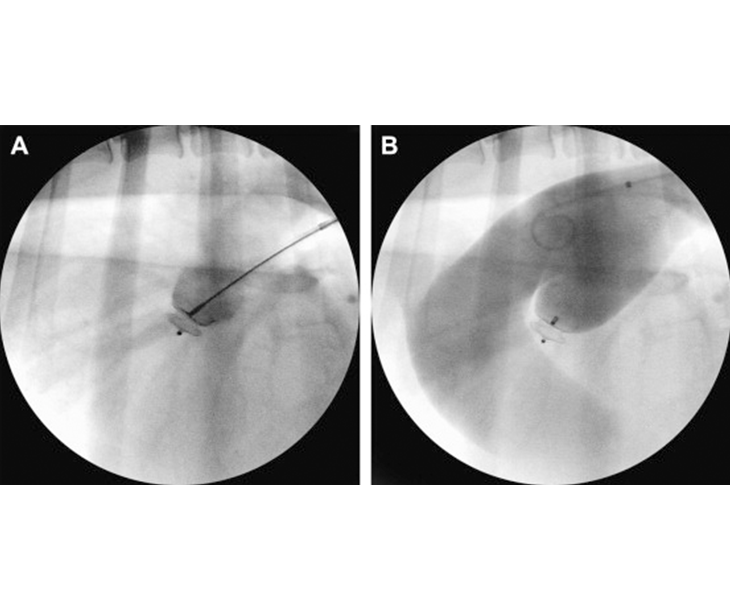

심장사상충 제거술

주로 개와 고양이에서 발생하는 심장사상충증을 치료하기 위한 절차입니다. 먼저 영상 검사와 혈액 검사를 통해 심장사상충의 위치와 개수를 파악하고, 환자의 건강 상태를 평가한 후 마취를 시행합니다. 수술 후 환자는 회복실에서 상태를 관찰받으며, 합병증으로 출혈, 감염, 혈전 등이 발생할 수 있어 주의가 필요합니다. 이 절차는 숙련된 의료진과 최신 장비가 필요하며, 환자의 상태에 따른 맞춤형 접근이 중요합니다.